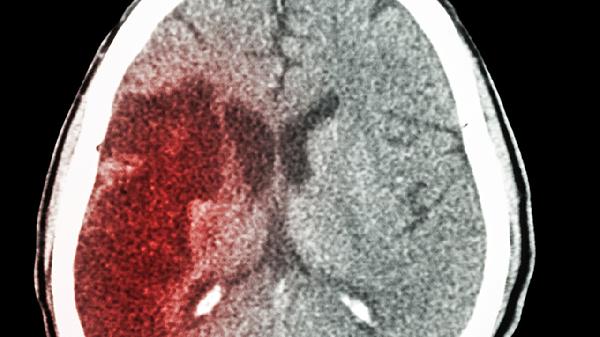

脑积水手术的核心目标是解除颅内高压和脑脊液循环障碍,避免脑组织受压导致的不可逆损伤。术后患儿若未遗留严重神经系统后遗症,且下丘脑-垂体功能未受损害,其生长激素分泌通常可维持在正常水平。此时通过均衡营养摄入,尤其是保证优质蛋白、钙质及维生素D的补充,配合适度的纵向运动如跳绳、篮球等,骨骼生长板可按照遗传潜力正常发育。临床观察显示,多数术后患儿在定期复查脑脊液循环状态稳定后,身高增长速度与同龄儿童无显著差异。

少数合并复杂病情的患儿可能出现术后生长迟缓,多见于术前已存在严重脑损伤或继发内分泌功能障碍的情况。这类患儿因下丘脑-垂体轴受损可能导致生长激素缺乏,需通过儿科内分泌科评估后进行激素替代治疗。同时伴随的肌张力异常或运动障碍可能限制日常活动量,需康复训练改善运动功能以促进骨骼应力刺激。此类特殊情况下,身高发育需个体化医疗干预与长期随访监测。